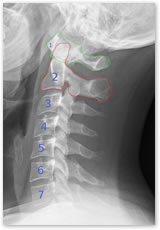

その秘密は上部頸椎のズレにありました。

脳からの神経伝達が正常に伝わらないと、患者さんのいう主訴である、慢性的腰痛、肩こり、頭痛、背中痛、自律神経の乱れ、不定愁訴など、体に様々な不調が起こります。

この脳の神経伝達を妨害しているのが、後頭骨と上部頸椎1番2番のズレです。

頭蓋骨を支える後頭骨、それに繋がる頸椎にズレが生じると、脳からの神経伝達が阻害されて、全身の機能が正常に働かなくなってしまうのです。

この上部頸椎のズレを治すと身体全体の機能が正常に戻って、患者さんが訴える主訴が消えるだけでなく患者さんの身体が治癒力を取り戻していくことが出来るのです。

上部頸椎は、第一頸椎12通り、第二頚椎14通りの歪みがあります。

さらに、後頭骨へのジョイントの歪みを合わせるとなんと数十通りもの歪みの組み合わせがあるわけです。

この頸椎がどちらにズレているか?によって背骨がどうズレているかを割り出します。

この一連の頸椎検査で、最終的に背骨がどちらにズレているのかが分かり

背骨の調整法がきまる大切な検査

上部頸椎に一切触れることなく骨盤から上部胸椎までを施術することによって上部頸椎、下部頸椎いっさい調整することなく首の骨が万全な状態になるのがDRTの特徴です。